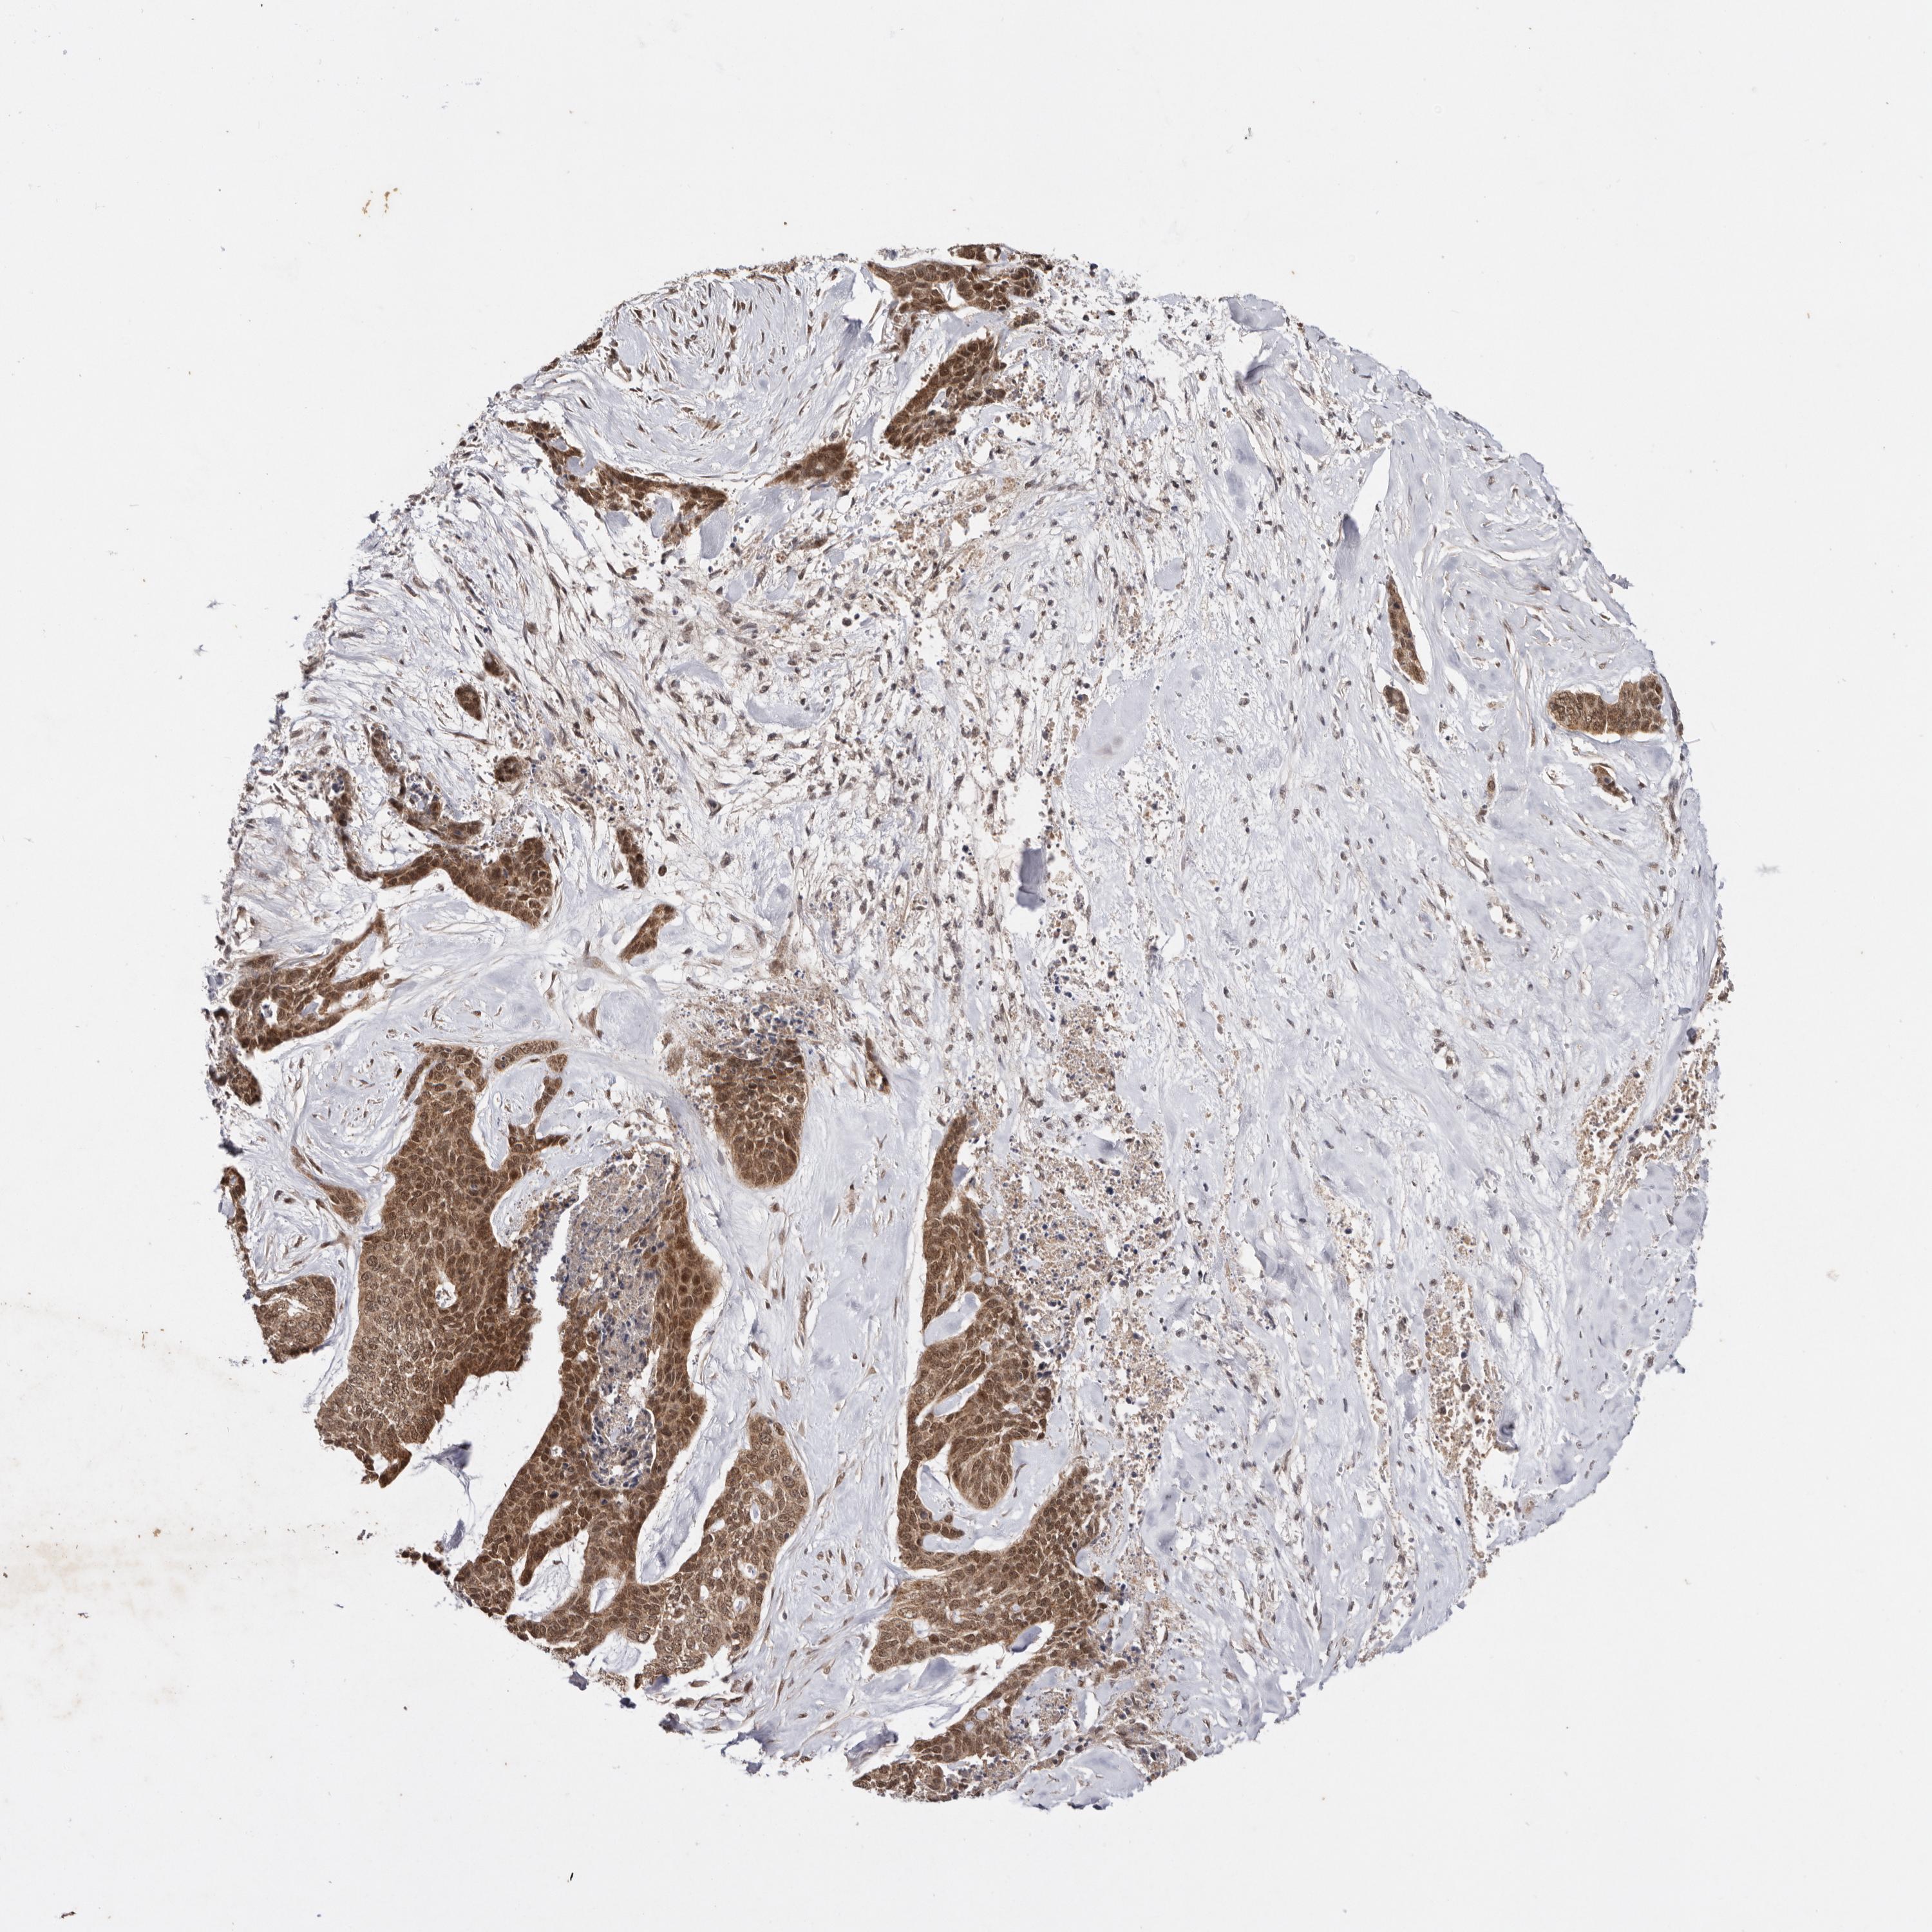

SKIN CANCER - Protein expressioni

A mouse-over function shows sample information and annotation data. Click on an image to view it in a full screen mode. Samples can be filtered based on level of antibody staining by selecting one or several of the following categories: high, medium, low and not detected. The assay and annotation is described here.

Antibody stainingi

Antibody staining in the annotated cell types in the current human tissue is reported as not detected, low, medium, or high, based on conventional immunohistochemistry profiling in selected tissues. This score is based on the combination of the staining intensity and fraction of stained cells.

Each image is clickable and will lead to virtual microscopy that enables deeper exploration of all samples and also displays staining intensity scores, fraction scores and subcellular localization as well as patient and tissue information for each sample.

Antibody HPA028626

Staining

High

Medium

Low

Not detected

Intensity

Strong

Moderate

Weak

Negative

Quantity

>75%

75%-25%

<25%

None

Location

Nuclear

Cytoplasmic/membranous

Cytoplasmic/membranous,nuclear

Basal cell carcinoma